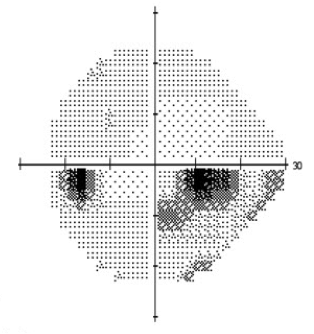

Automated static perimetry is the most common modality used to detect and monitor for progression of the field loss associated with normal tension glaucoma. Visual field defects may include those common to POAG including nasal step and arcuate scotoma. However, defects noted in NTG tend to be more focal and occur closer to fixation early in the disease (Figure 2a,b). Dense paracentral scotomas may characteristically be noted at initial diagnosis. For a full discussion of visual field testing see the main article “Standard Automated Perimetry.”

Figure 2: Standard automated perimetry of a) left and b) right eye in a patient with normal tension glaucoma. Note the dense inferior arcuate scotomas occurring near fixation with minimal involvement of periphery. The corresponding optic nerve head changes are seen in Figure 3.